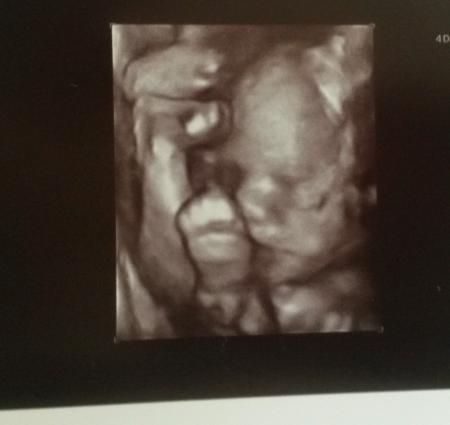

Bild 2: nuckelnd? Und beide Füße vor der Stirn